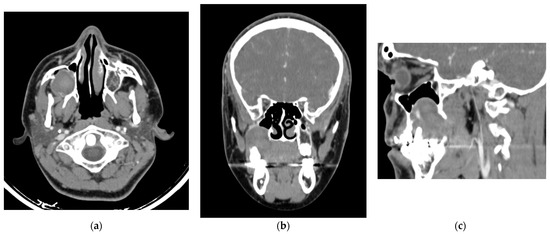

Background/Objectives: Tooth extraction is known to cause both bone loss and soft tissue collapse, changes that can complicate implant placement. While alveolar ridge preservation techniques have been proposed to limit these alterations, they often f...